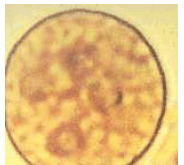

A imagem abaixo mostra um cisto de Entamoeba histolytica corado com lugol diluído.